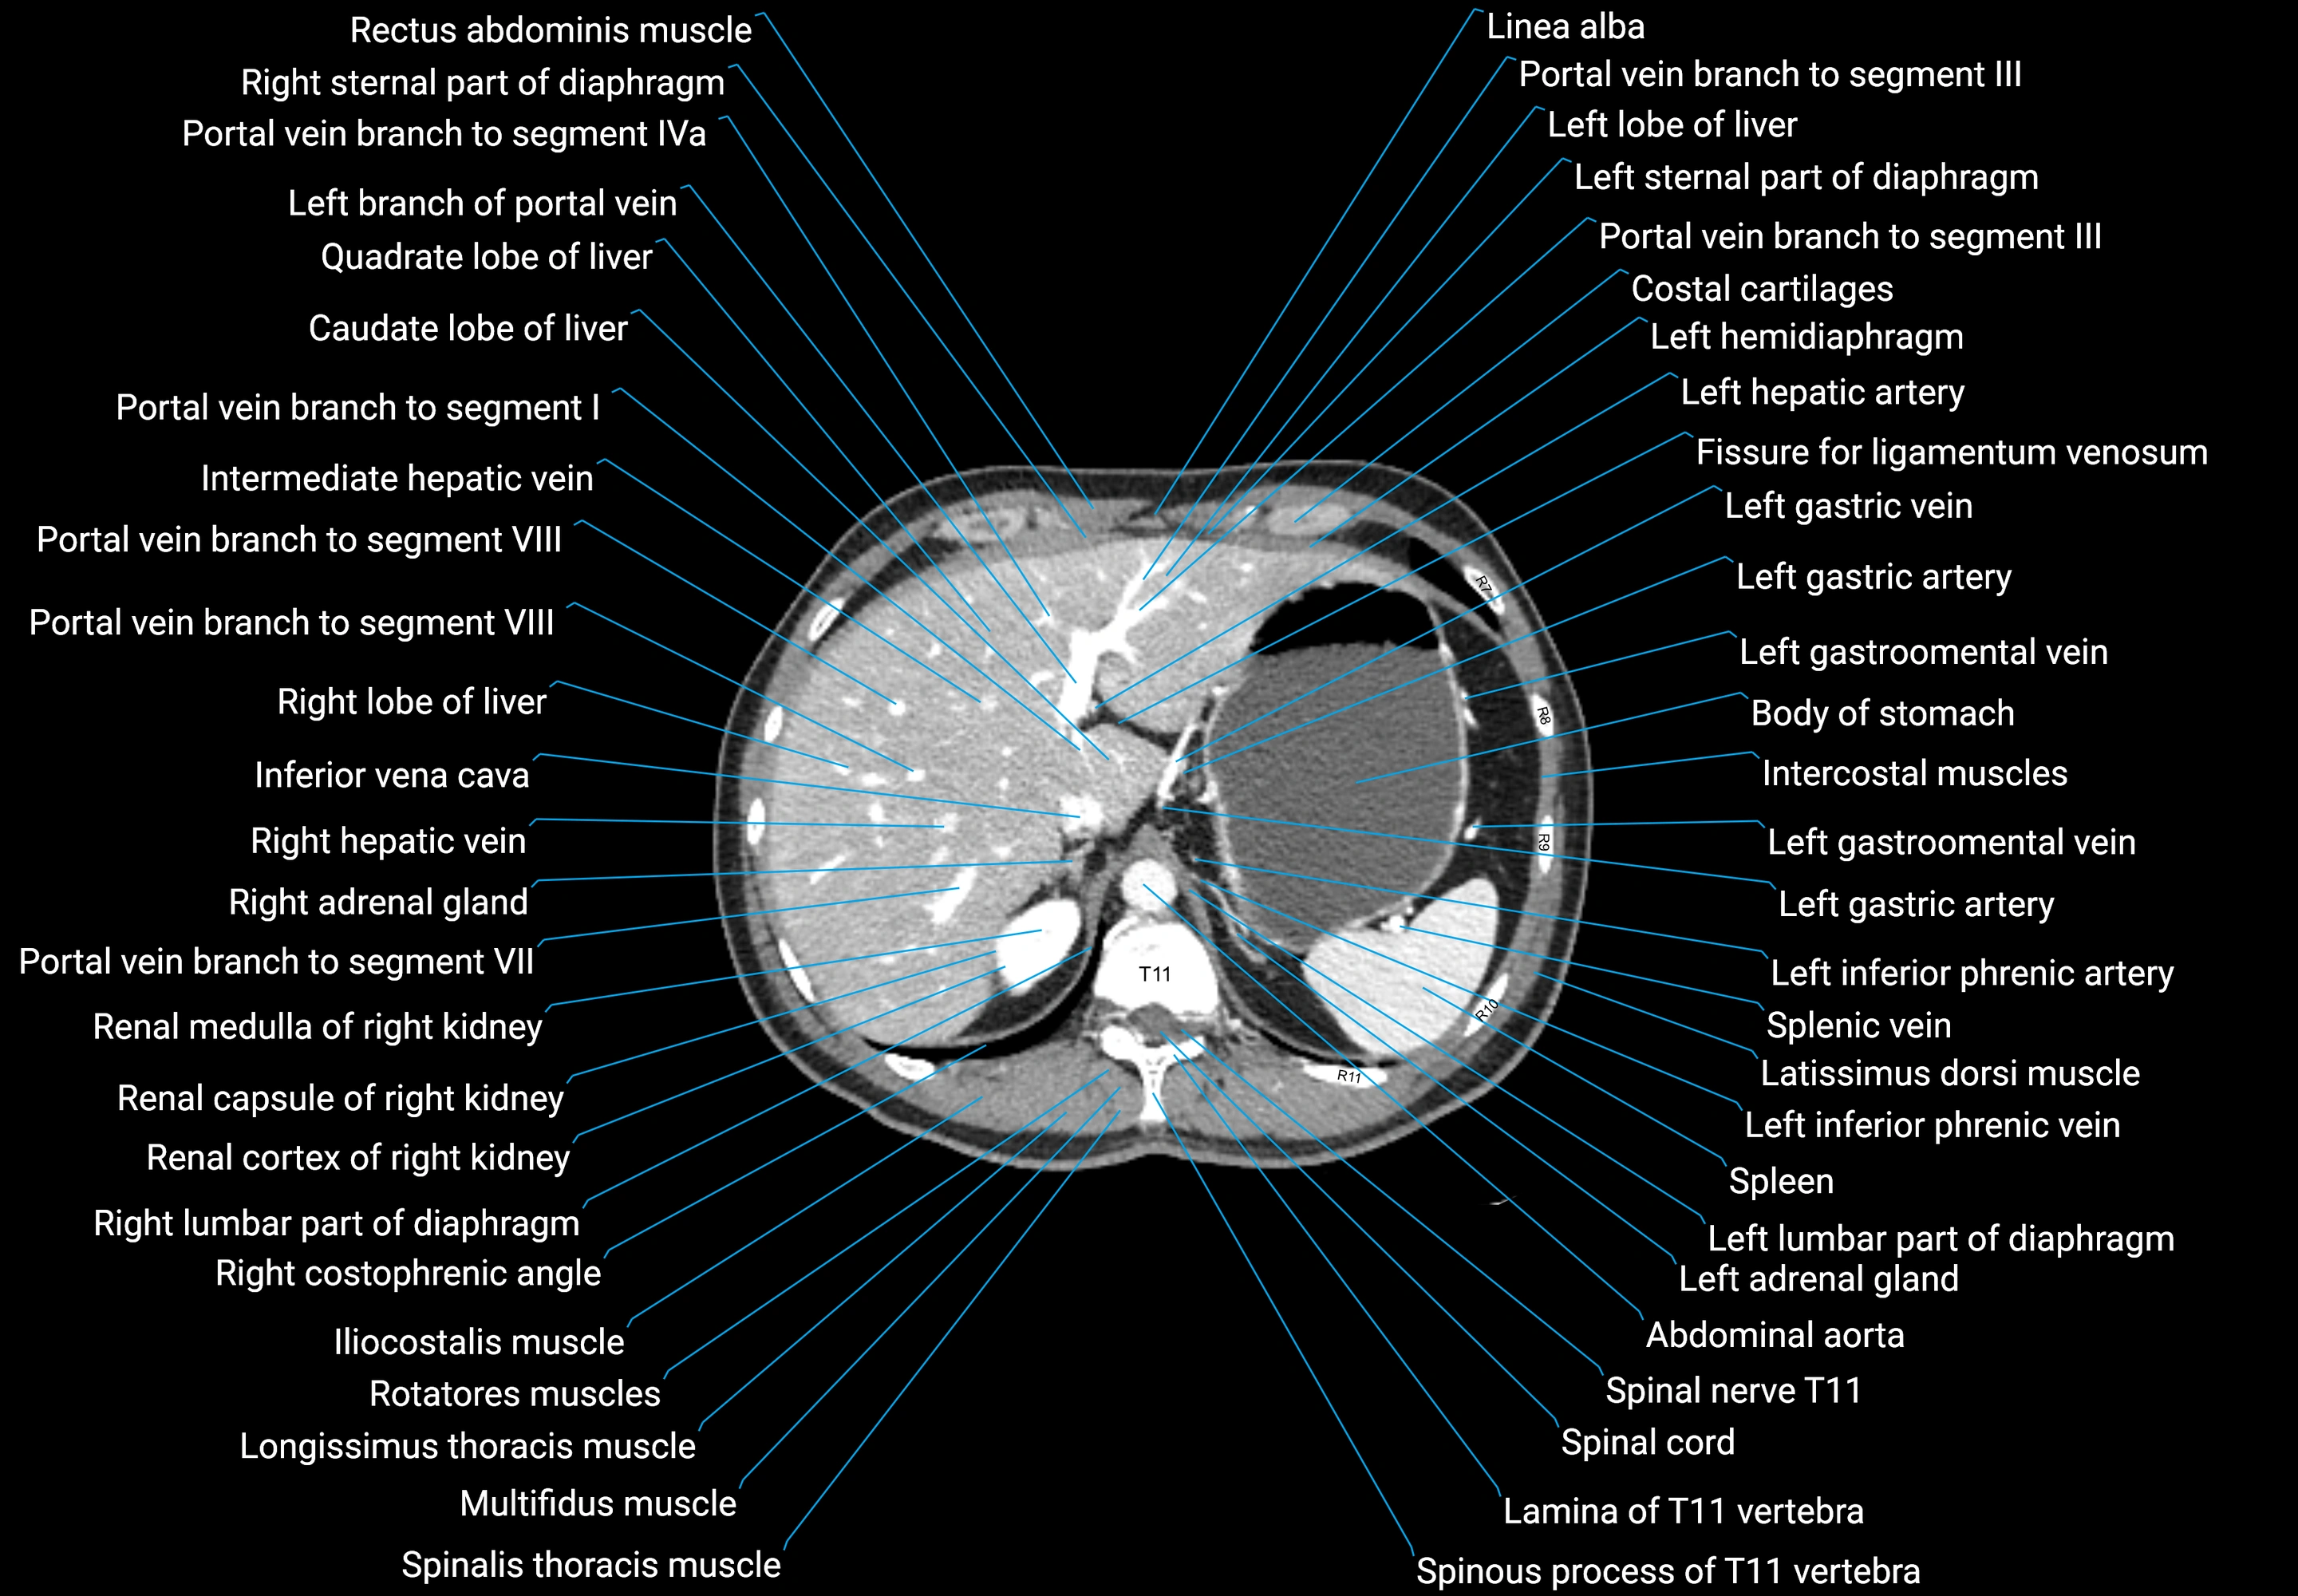

CT images